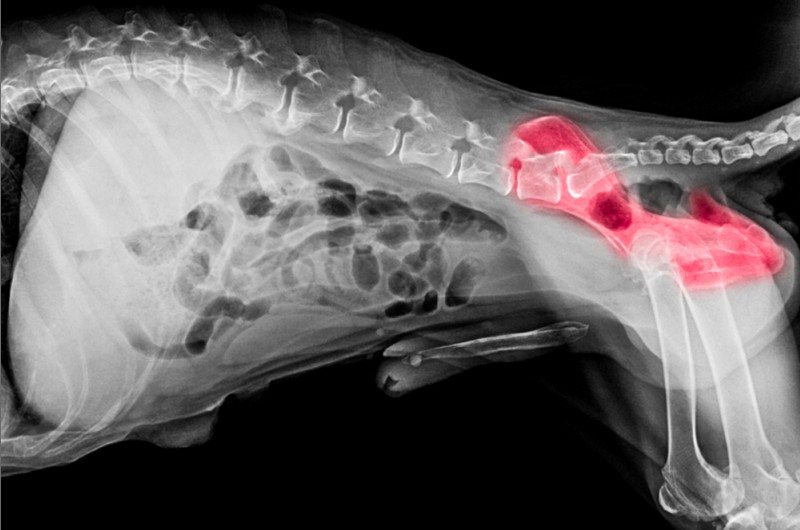

Trifft eins der genannten Anzeichen auf Ihren Hund zu, sollten Sie unverzüglich einen Tierarzt aufsuchen, um die Gelenke des Tieres röntgen zu lassen. Wird der Verdacht einer Arthrose bestätigt, sollten Sie mit dem Arzt besprechen, wie man die Krankheit in Zukunft behandeln sollte und die Beschwerden des Hundes langfristig lindern kann.

Bei Verdacht auf Arthrose oder auch anderen Gelenkschmerzen bei Hunden sollte man unbedingt ein Röntgenbild machen lassen. Nur so lassen sich größere Schäden beurteilen. (#2)